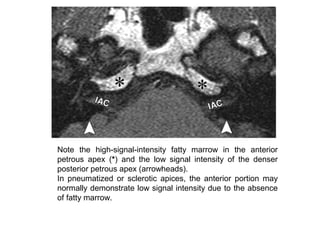

Note the high-signal-intensity fatty marrow in the anterior

petrous apex (*) and the low signal intensity of the denser

posterior petrous apex (arrowheads).

In pneumatized or sclerotic apices, the anterior portion may

normally demonstrate low signal intensity due to the absence

of fatty marrow.